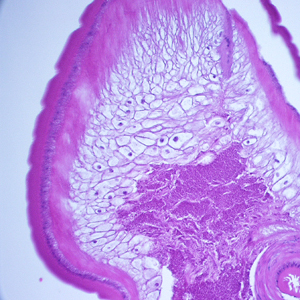

Case #248 – March, 2009

A 36-year-old immigrant from Mozambique presented to his health care provider with heartburn and chronic right abdominal pain. All previous ova and parasite (O&P) examinations were negative. An endoscopy was performed, upon which a worm-like object was observed in the ascending colon near the ileocecum. The suspicious object, measuring approximately 7 mm in length, was removed, collected in 10% formalin, and sent to Pathology for work-up. The object was sectioned, stained with hematoxylin and eosin (H&E) and reviewed by the attending pathologist, who in turn captured the following images and sent them to DPDx for telediagnosis assistance. What is your diagnosis? Based on what criteria?

Figure A